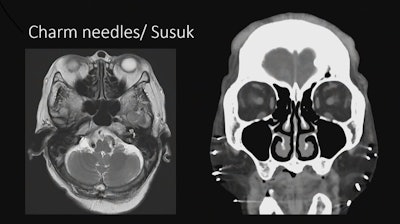

Imaging showing implanted charm needles in a patient.Image courtesy of Sumeet Kumar, MD

Kumar also noted a few safety concerns in cases with “local flavor,” such as patients with magnetic eyelashes and implanted subcutaneous charm needles. Charm needles are placed by shamans, so there is a spiritual belief associated with them related to enhancing a person’s beauty or energy, she said.

“And the bearer is not supposed to disclose it. They will not tell you that they’ve got them,” Kumar said.

A recent study determined that the needles are made mostly of gold, so they have been deemed safe in patients undergoing MRI scans, and Kumar said she and her colleagues have imaged multiple patients with these needles with no adverse events.